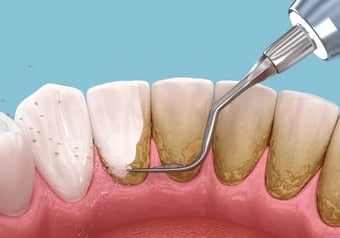

Tooth Ultra Sonic Cleaning